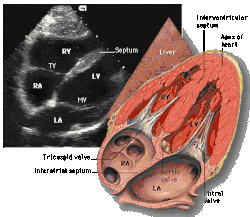

|  Subcostal four chamber |  Apical four chamber |  Parasternal long axis  |  Parasternal short axis  | ||||||||

| Each figure contains a TTE with a black background, and a corresponding colored illustration. | Patrick J. Lynch and C. Carl Jaffe, Yale University, 2006. | ||||||||||

| Click on a figure to enlarge it and see some parts of the heart identified. RV, right ventricle; LV, left ventricle; RA, right atrium; LA, left atrium; TV, tricuspid valve; MV, mitral valve; AV, aortic valve; RVOT, right ventricular outflow tract; LVOT, left ventricular outflow tract | |||||||||||